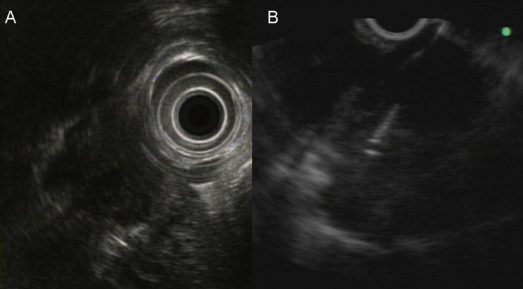

When it was confirmed in the EUS image that the needle had been properly inserted into the lesion, the stylet of the needle was removed and the needle was connected to a syringe with a negative pressure (0∼10 mL). The needle was then moved back and forth > 10 times to obtain a tissue specimen (Fig. 1 ). After withdrawing the needle, the target lesion was observed by EUS to determine whether any changes (shape or internal texture) occurred in the tumor. The adjacent tissue was also carefully observed to determine whether there were any changes, such as hematoma. Because on-site cytopathologic evaluation was not available in our hospital, the needle punctures were repeated several times (2∼5 times puncture when possible) until there was gross evidence that tissue particles had been obtained, or the maximal number of punctures had been performed. At the end of the procedures, absence of bleeding at the point of puncture was confirmed endoscopically. Aspirates were prepared on glass slides and fixed in absolute alcohol solution for the cytological study. When sufficient materials had been obtained, the specimens were also put in the formalin solution for pathological evaluation (hematoxylin-eosin staining and other immunohistochemical stains as necessary).

Figure 1. A patient with pancreatic head neuroendocrine tumor and mediastinal lymph node metastasis diagnosed by endoscopic ultrasound-guided fine needle aspiration (EUS-FNA) cytopathology. (A) The EUS image of the mediastinal lymph node by radial echoprobe and (B) the EUS image of the performance of EUS-FNA. |